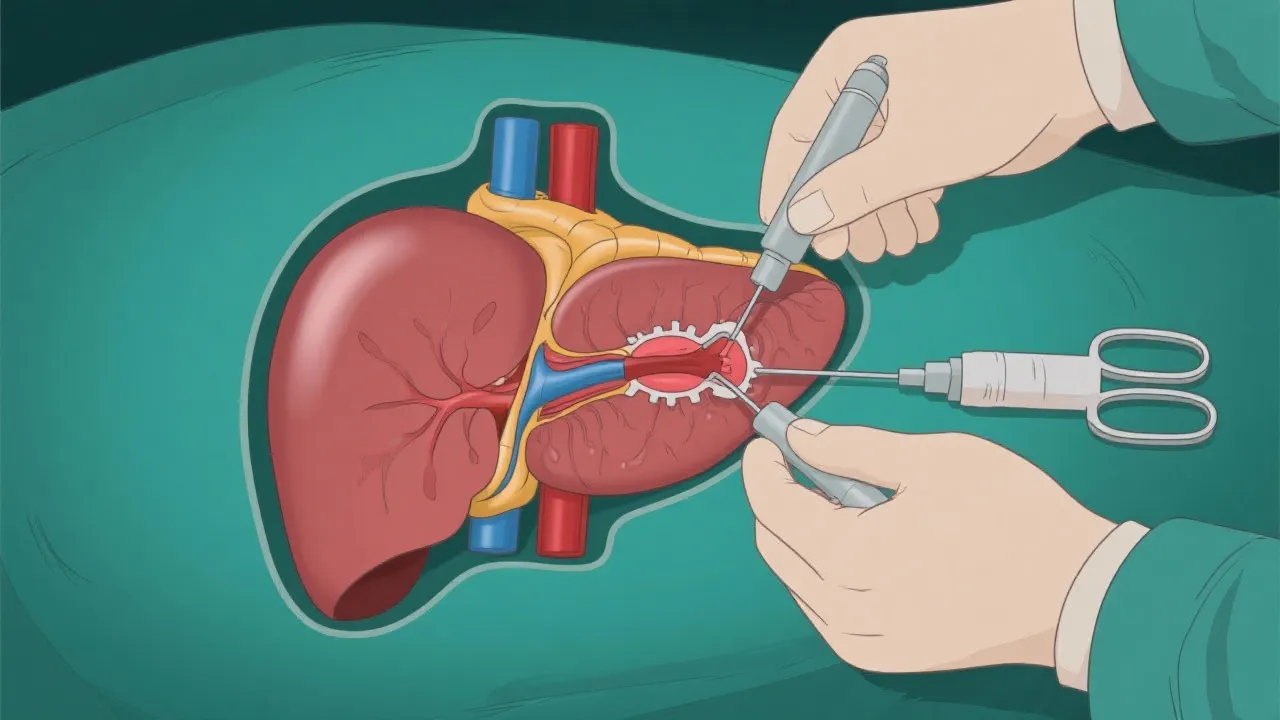

Understanding Hepatitis E and Liver Transplant

Understanding Hepatitis E and Liver Transplants

Understanding Hepatitis E and Liver Transplants

Understanding Hepatitis E and Liver Transplants

Understanding Hepatitis E and Liver Transplants

Hepatitis E and Liver Transplant

Understanding Hepatitis E and Liver Transplant

Understanding Hepatitis E and Liver Transplants

Navigating Hepatitis E and Liver Transplant

Navigating Hepatitis E Liver Transplants

Hepatitis E and Liver Transplant Insights

Hepatitis E and Liver Transplant